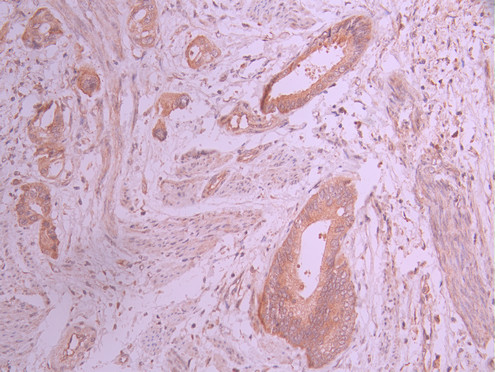

IHC image of CSB-RA795810A0HU diluted at 1:100 and staining in paraffin-embedded human cervical cancer performed on a Leica BondTM system. After dewaxing and hydration, antigen retrieval was mediated by high pressure in a citrate buffer (pH 6.0). Section was blocked with 10% normal goat serum 30min at RT. Then primary antibody (1% BSA) was incubated at 4°C overnight. The primary is detected by a Goat anti-rabbit polymer IgG labeled by HRP and visualized using 0.05% DAB.